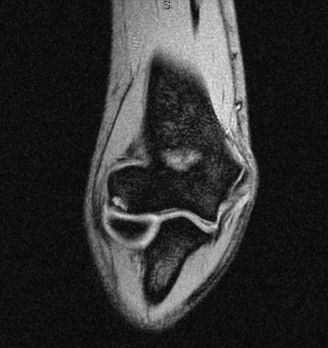

Figure 1: Pre-operative MRI displaying a significant osteochondritis dissecans lesion of the capitellum with associated edema and possible fragment instability. Such imaging is critical for surgical planning.

Magnetic Resonance Imaging (MRI):

The preferred advanced imaging modality. MRI provides detailed information on cartilage integrity, subchondral bone edema, the presence of a fluid signal at the lesion-host interface (indicative of instability), and identification of loose bodies. T1, T2, and proton density sequences with fat suppression are essential.

- MRI: The gold standard for assessing cartilage integrity, subchondral bone edema, lesion stability (presence of fluid signal at the lesion-host interface), and identifying loose bodies. T1-weighted, T2-weighted, and proton density fat-suppressed sequences are typically used.

Figure 1: Pre-operative MRI displaying a significant osteochondritis dissecans lesion of the capitellum with associated edema and possible fragment instability. - CT Scan: Useful for detailed bony anatomy, assessing fragment size, degree of displacement, and surgical planning, especially for fixation. Arthro-CT may provide better visualization of cartilage defects.